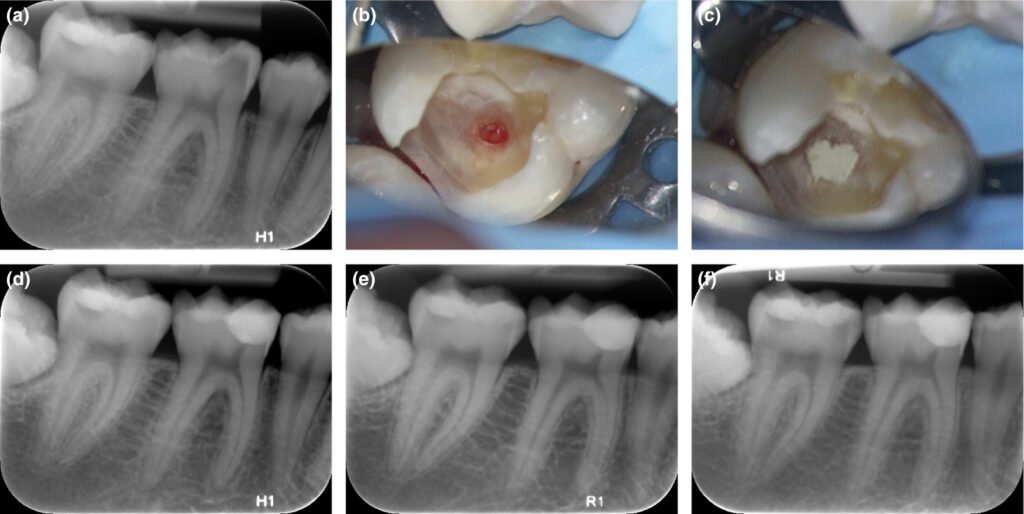

Illustration radiographique d'une carie profonde avec dentine réactionnelle

Cas Clinique 1 : Dentine Réactionnelle et Gestion d’une Carie Profonde

Patient : Homme de 34 ans, sans antécédents médicaux notables. Consultation pour une « douleur au froid » sur la 36 (première molaire mandibulaire gauche).

Présentation clinique : Douleur brève au contact du froid, disparaissant en moins de 10 secondes après retrait du stimulus. Absence de douleur spontanée. À la radiographie rétroalvéolaire, lésion carieuse profonde mésiale, avec image de dentine réactionnelle visible sous la carie (zone plus radio-opaque entre la lésion et la pulpe).

Problématique : La lésion est profonde mais la pulpe a répondu par une dentinogenèse réactionnelle active. Le diagnostic est une pulpite réversible sur carie profonde.

Prise en charge : Excavation carieuse partielle en laissant en place la dentine affectée la plus profonde (curetage sélectif), mise en place d’un fond de cavité à base de Biodentine, puis restauration composite.

Évolution attendue : Dans la grande majorité des cas, la vitalité pulpaire est maintenue. Un contrôle à 6 mois confirme la persistance de la vitalité et l’absence de signes périapicaux. Ce cas illustre l’importance de respecter la dentine réactionnelle : la retirer serait supprimer la défense naturelle de la pulpe.

Prise en charge : Coiffage pulpaire direct au MTA (Mineral Trioxide Aggregate) sous champ opératoire rigoureux (digue). Restauration provisoire étanche. Contrôles cliniques et radiographiques à 3, 6 et 12 mois.

Évolution attendue : Formation d’un pont dentinaire réparateur en 4 à 8 semaines, confirmé radiographiquement. Poursuite de l’apexogenèse. Ce cas illustre le concept de dentinogenèse réparatrice : les cellules progénitrices pulpaires recrutées reforment une barrière calcifiée qui protège la pulpe et permet la poursuite du développement radiculaire.